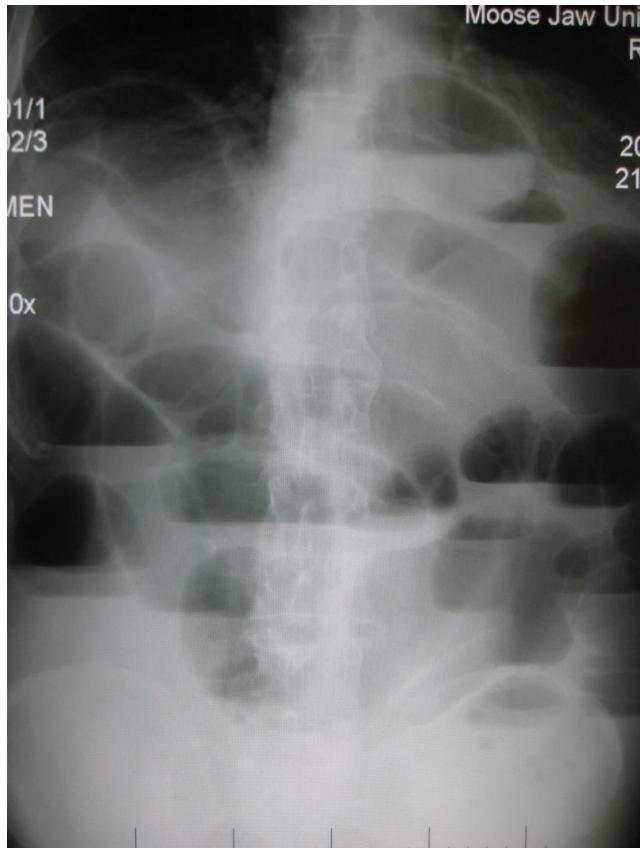

Small Intestinal Obstruction

- Diagnosis: Small Intestinal Obstruction.

- X-ray Findings: Multiple air-fluid levels on erect abdominal X-ray; distended bowel loops.

- Clinical Presentation:

- Abdominal distention.

- Constipation and vomiting.

- Decreased/hypoactive bowel sounds.